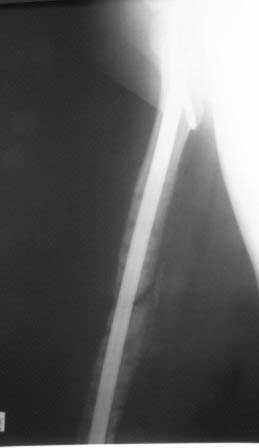

Результат нашего лечения:  Произведено удаление пластины МIPO. Интрамедуллярный остеосинтез с рассверливанием канала. На 2-е сутки после операции больная передвигается при помощи костылей, с полной нагрузкой на оперированную конечность, болей в области перелома нет.

Фотографии в приложении.